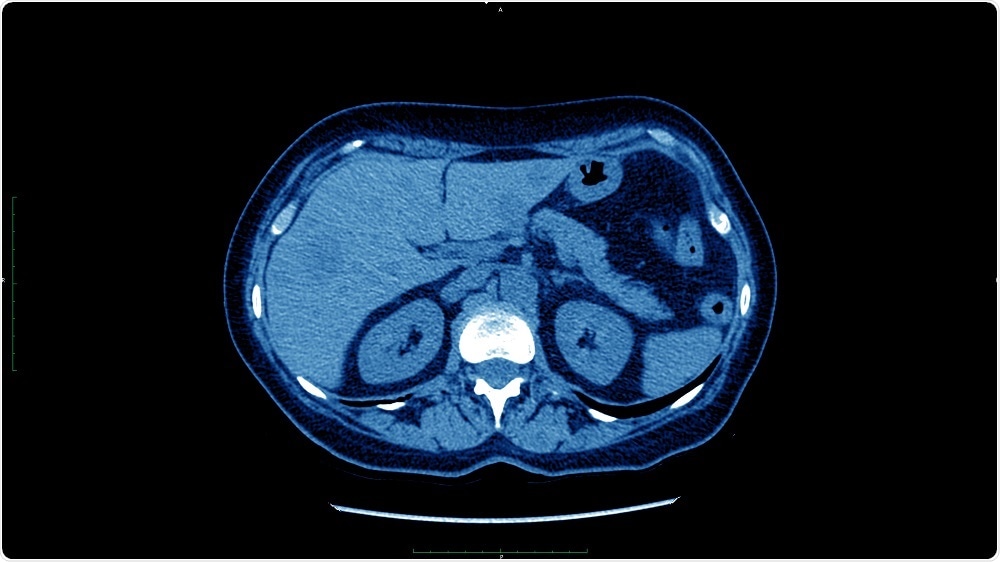

Credit: dade72/Shutterstock.com

Liver cancer screening in patients with chronic liver disease has traditionally been performed using an abdominal ultrasound. While ultrasound is readily available and noninvasive, it misses many cancers when they are small.